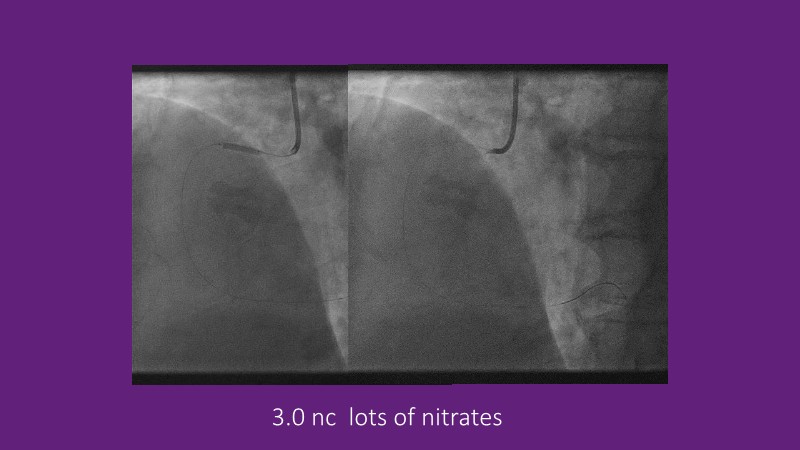

Explore cutting-edge strategies for optimizing drug-coated balloon (DCB) procedures in this session. Uncover practical tips to improve outcomes, review key indications, and examine international consensus on DCB use. Case presentations and expert discussions offer insights to refine your approach.

- To learn the tips and tricks to improve the result with drug coated balloon strategy